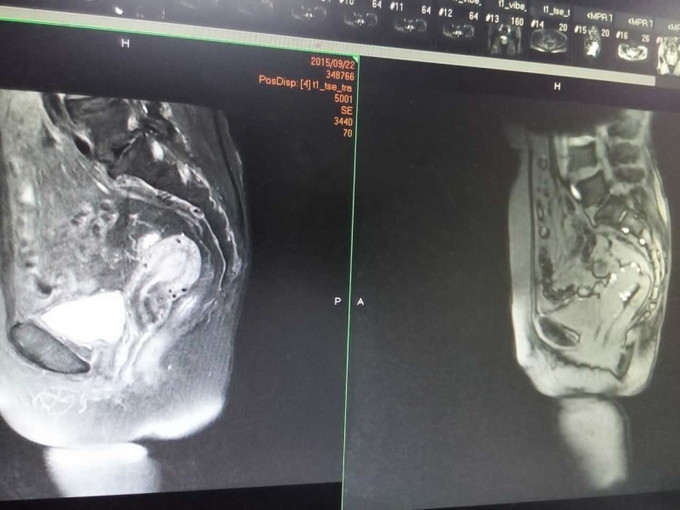

妇科查体:外阴:发育正常。阴毛分布正常;阴道:通畅,阴道分泌物呈血性,无臭味。宫颈:稍小,质中,一度糜烂,宫口未见明显组织物,未见活动性出血。宫体:前位,质中,稍小,无压痛,活动好。双附件:未扪及明显包块,无触痛。 辅助检查: 妇科肿瘤标志物未见明显异常。彩超(外院):子宫后位,3.9*2.8*3.1cm,形态正常,肌层回声不均,可见散在强回声光斑,宫内膜居中,回声不均,厚1.8cm。左侧附件区显示欠清,右侧附件区未见明显异常回声。超声提示:子宫内膜增厚不均,建议进一步检查;子宫肌层钙化灶。 分段诊刮病理:子宫内膜大部分区域为复杂性增生的宫内膜,局部可见复杂乳头形成,并可见腺体“背靠背”、“共壁”及筛状结构形成,局部细胞核大、深染,部分可见核仁,病变符合子宫内膜样腺癌。 我院B超: 经阴道+彩超检查: 子宫长径41mm,前后径33mm,横径37mm,稍小。 子宫内膜难辨。 宫腔内见高回声区,范围23mm×15mm,边界清,与肌层分界清,彩超显示病灶内可见少量彩色血流信号并探及中等阻力动脉血流频谱。 肌层回声欠均。 双侧卵巢显示不清,双侧附件区未见明显异常肿块。子宫腔内异常回声,结合病史,考虑子宫内膜Ca。 MR检查所见: 平扫见子宫体积不大,轮廓光整,子宫体稍后倾。子宫内膜弥漫性增厚,最厚处约9mm,后壁结合带信号变薄、中断,阴道未见异常信号和增厚。增强扫描子宫内膜不均匀明显强化,与后壁肌层信号分界不清。双侧附件区未见异常信号,盆腔内未见异常信号和肿块,盆腔淋巴结未见增大。 检查结论/诊断:考虑子宫内膜癌,侵犯后壁肌层;双附件未见异常,盆腔淋巴结未见增大。